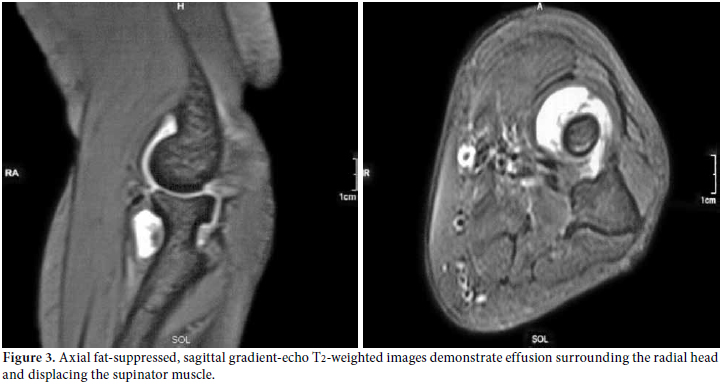

Plain radiography of the left elbow, musculoskeletal ultrasonography (US), and magnetic resonance imaging (MRI) were used to make a visual representation of the pathology. The plain radiography showed soft tissue swelling with a normal articular surface. The US assessment (7.5 MHz linear transducer, gray scale, General Electric Medical Systems, Milwaukee, Wisconsin, USA) pointed out an “eye-shaped”, demarcated, hypoechoic bulging mass with regard to articular effusion that was in close contact with the “contoured eyebrow-shaped” fascicular PIN. It had swelled to 2 mm compared with 1 mm on the asymptomatic right side (Figure 2). The MRI indicated hyperintense, demarcated fluid around the radial head, neck, and distal humerus (Figure 3).